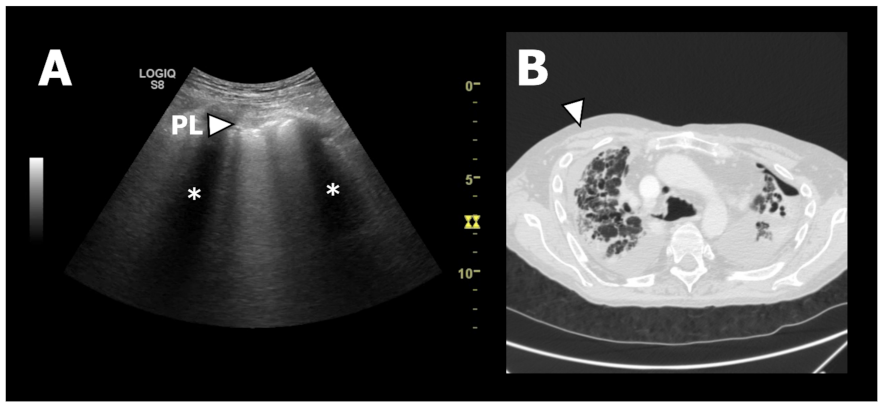

In total 350 LUS records (25 patients with each 14 LUS zones) were reviewed and interpreted with findings as presented in Table 2. A significant majority of patients with RAS presented with pleural thickening, when compared to patients with BOS (Figure 3). In RAS patients, the pleural line was solely characterised as being fragmented, and in addition significantly thicker than the pleural line observed in BOS patients corresponding to 5.6 mm and 2.9 mm, respectively (Supplementary Table S1). Additionally, the proportion of patients with ≥3 B-lines was more predominant among RAS patients than in BOS patients. No consolidations were identified in either group.

Figure 3.

LUS and HRCT findings from a patient with RAS. (A): Lung ultrasound image from zone R1. At the top of the chest wall structures can be seen as a grey area. Just below the chest wall the pleural line (PL) can be seen as a horizontal white line. It has an abnormal appearance since it is thickened and fragmented. The two black areas (*) is caused by “shadowing” due to the ultrasound waves being absorbed and reflected by the ribs. (B): Axial HRCT image of the upper lobes showing fibrotic pleural and septal thickening consistent with PPFE. The white arrow corresponds to LUS zone R1 presented in A.